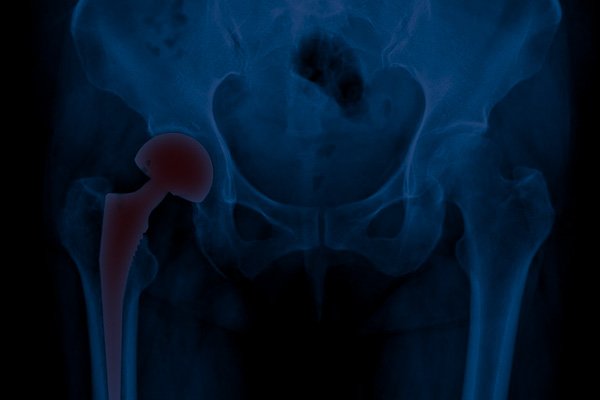

Artroplastia total do quadril

A artroplastia total do quadril trata casos graves de artrite, substituindo a cabeça femoral danificada por uma prótese fixada na bacia.